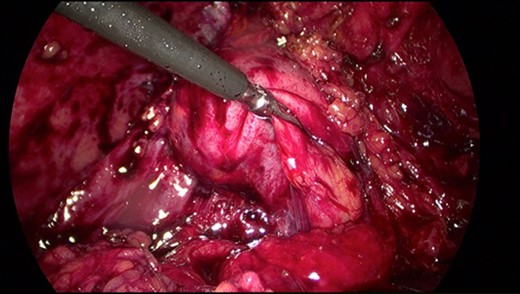

The patient presented to the hospital 4 months after the initial operation with right upper quadrant pain. CT abdomen established the appearance of a normal gallbladder despite his history of subtotal cholecystectomy (Fig. 2). He underwent an elective laparoscopic cholecystectomy 1 month later, which revealed an apparently complete gallbladder that was extensively walled off by omentum. An intraoperative image is shown in Fig. 3.

Intraoperative image of Hartmann's pouch (held by graspers) in continuity with a reformed gallbladder.